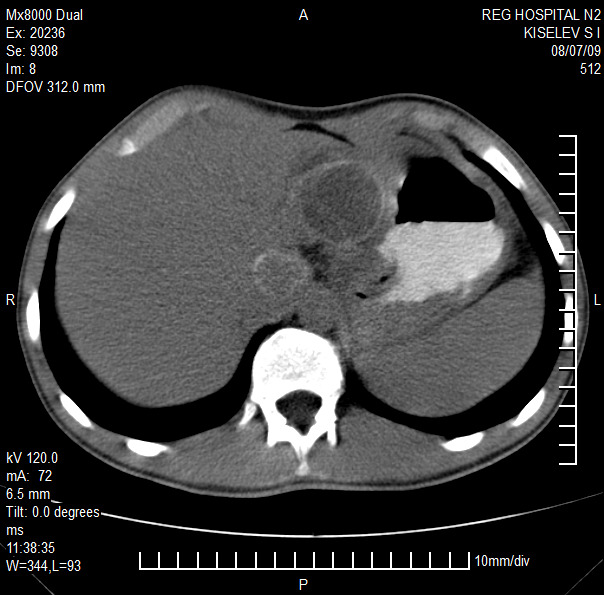

Представлены клинические наблюдения редкого осложнения эхинококкоза печени – прорыва эхинококковой кисты в желчные протоки. Осложнение стало причиной обструкции желчных протоков, механической желтухи и холангита. Освещены этапы диагностики, роль УЗИ в выявлении осложнений эхинококкоза печени, рассмотрены способы минимально инвазивного лечения с применением эндоскопических и чрескожных технологий под контролем лучевых методов.